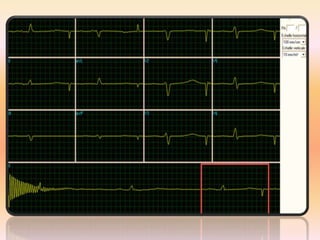

RYTHME SINUSAL REGULIER

complexes QRS.